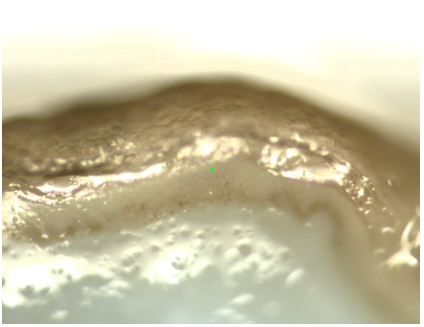

Hình 1. Hình ảnh mô da tươi quan sát dưới kính hiển vi quang phổ Raman, vật kính 10x.

Hình 5. Hình ảnh mô da cố định formalin quan sát dưới kính hiển vi quang phổ Raman, vật kính 10x.